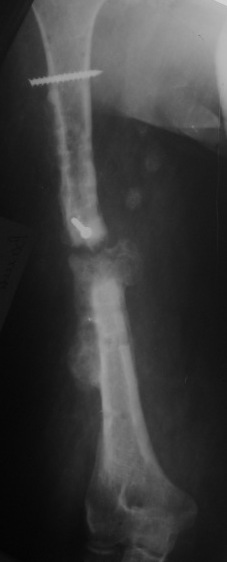

Несросшийся перелом диафиза

Уважаемые коллеги, пациентка лечится с переломом диафиза плеча 1.5 года.

Первоначально синтез пластиной,через 1 год перелом фиксаторов, АВФ на 4 месяца, 2 месяца в гипсовой лонгете и повторная травма. Планируется синтез интрамедуллярным гвоздем. Стоит ли максимально плотно подгонять концы отломков, удалять избыточную костную мозоль или достаточно жесткого синтеза с плотной посадкой гвоздя с ликвидацией ренгенологического диастаза?